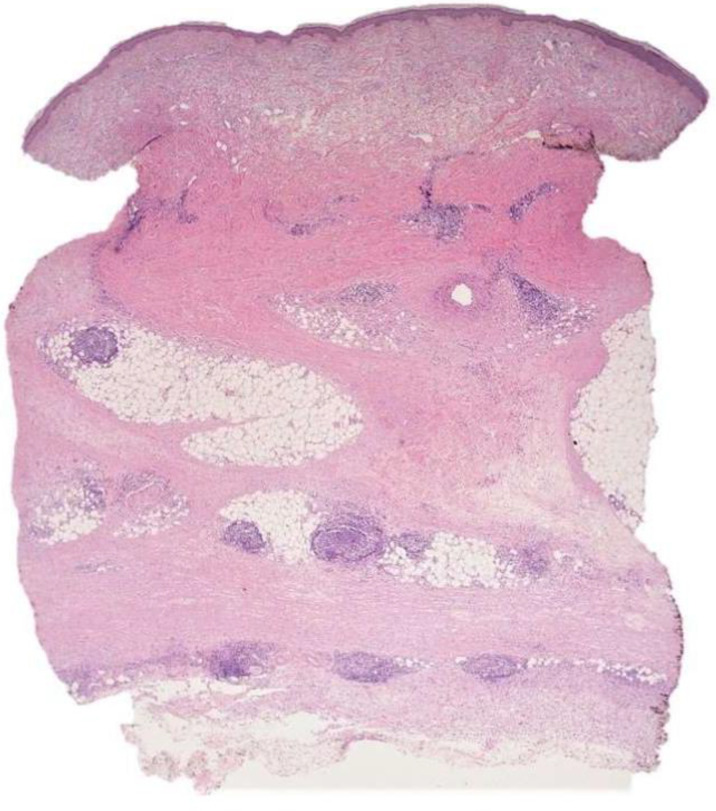

Morphea profunda or subcutaneous (deep) morphea is a variant of localized morphea, characterized by one or more ill-defined, deep sclerotic plaque. Preferential sites are the abdomen, trunk, sacral area, or extremities. The presence of hyperplastic lymphoid follicles in the context of the sclerotic bands of morphea is rarely described. Localized scleroderma is sustained by a profibrotic inflammatory profile. Transforming growth factor-β (TGF-β), an imbalance between functional subclasses of T-lymphocytes (innate immune cells) has a role in activate collagen deposition. In this case report, we present two cases of morphea profunda with lymphoid follicular hyperplasia. A systematic review of the literature on the pathophysiology of localized scleroderma is also presented, with particular reference to the presence of lymphoid structures.